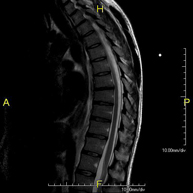

- Thoracic spine MRI

This non-invasive diagnostic procedure uses an electromagnetic field and radio waves (from a transmitter and receiver) to acquire high-definition anatomical images of the thoracic spine. It is a radiation-free procedure. Indicated for: trauma, degenerative problems, hernias, tumours.

- Lumbar spine MRI

This non-invasive diagnostic procedure uses an electromagnetic field and radio waves (from a transmitter and receiver) to acquire high-definition anatomical images of the lumbar and sacral regions. It is a radiation-free procedure. Indicated for: trauma, sciatica, herniated discs, tumours, infections.